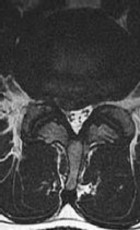

Figures 1 through 3 show sagittal and axial MRIs and a radiograph from a

77-year-old woman with leg pain when standing and walking of 1 year duration. The pain improves when she leans forward. She has been in physical therapy, taken oral analgesics, and had epidural injections with minimal relief. What is the best next step?

4. Microdiskectomy Discussion: B

The patient has lumbar stenosis of L2-3 and L3-4. She has no spondylolisthesis or instability. For her condition, spinal fusion plays a minimal role. She has no evidence of instability, and her condition can be addressed through laminectomy only. No role exists for microdiskectomy, because her disease results from a combination of ligamentum flavum hypertrophy and facet hypertrophy.